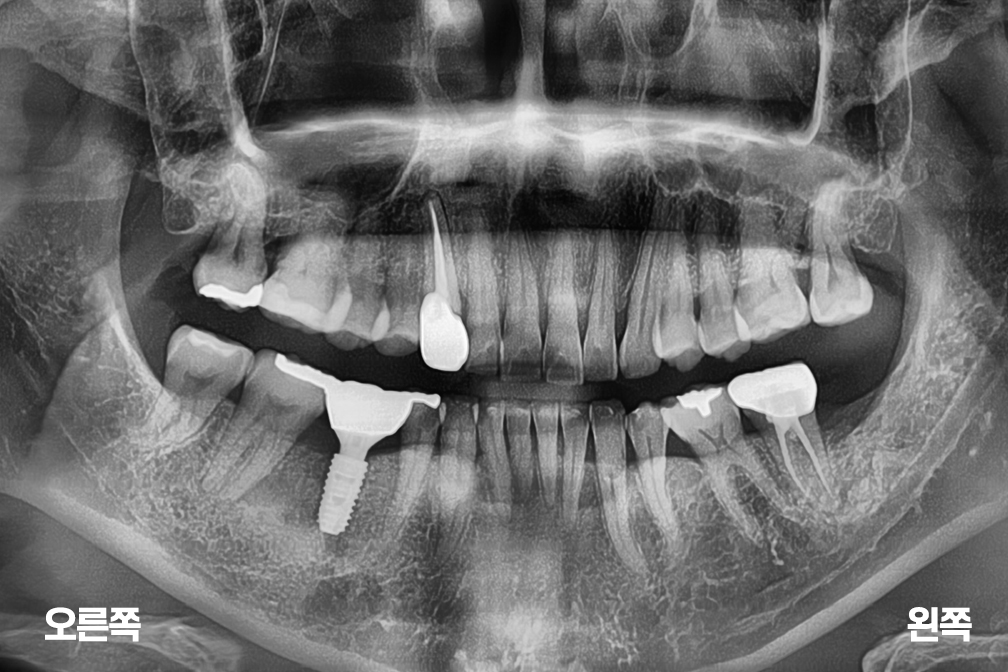

어금니 임플란트

Before 2025년 5월 16일